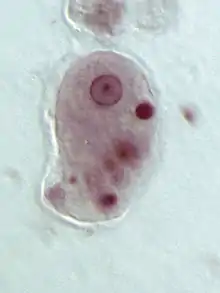

Trophozoites of E. histolytica with ingested erythrocytes

| Pathognomonic/diagnostic feature | Ingested RBC; distinctive nucleus |